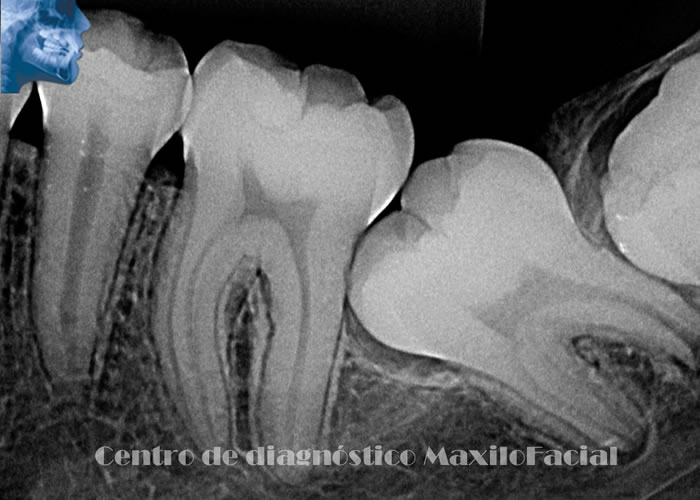

Radiografía Periapical

Término usado generalmente para describir a las radiografías “retro alveolares”, que son pequeñas radiografías intra-bucales para poder observar hasta tres piezas dentarias contiguas, se puede visualizar con mayor resolución que las radiografías extra-orales, sobre todo procesos infecciosos en el extremo apical de la raíz, lesiones cariosas o reabsorción del reborde óseo.

Dentro de las retro alveolares las técnicas más comunes son las de paralelismo, periapicales, de aleta de mordida, de desplazamiento, etc.

A continuación queremos mostrarle nuestra galería con algunas imágenes de casos llegados a Cedimax - Centro de Diagnóstico Maxilofacial, si requiriera más ejemplos de casos no dude en contactarse con nosotros.